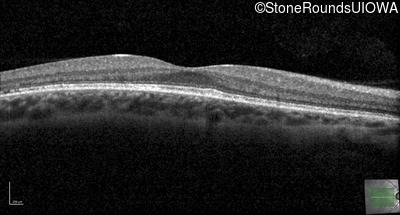

Optical Coherence Tomography - Right - 20/20

Exemplar / OCT Stack

OCT Stack